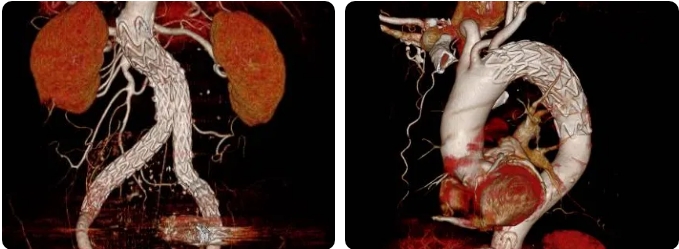

术中,血管外科专家团队通过屏幕所示影像,操作细细的导丝引入支架,不断调整位置及角度,准确定位后释放胸主动脉、腹主动脉支架主体,并对双侧髂内动脉瘤行栓塞术,最终成功隔绝了动脉瘤腔,让血流从支架内流过,不再冲击瘤体,有效避免动脉瘤破裂出血,并保留了腹腔脏器血供。

(隔绝瘤腔后)